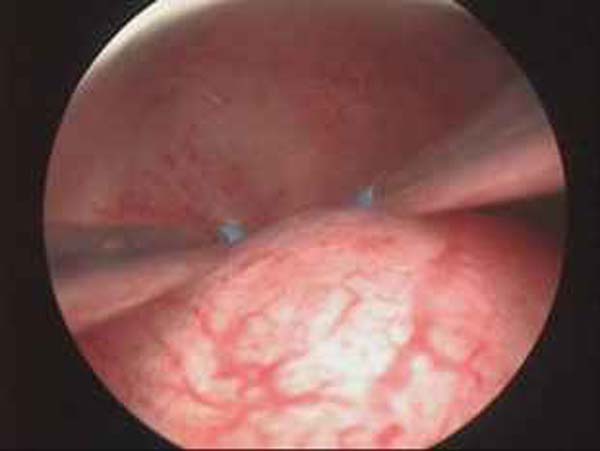

- Hystéroscopie - Hystéroscopie pour l'infertilité

- Résection hystéroscopique d'un septum utérin pour fausses couches à répétition

- Ablation de l'endomètre

- Photos de l’hystéroscopie